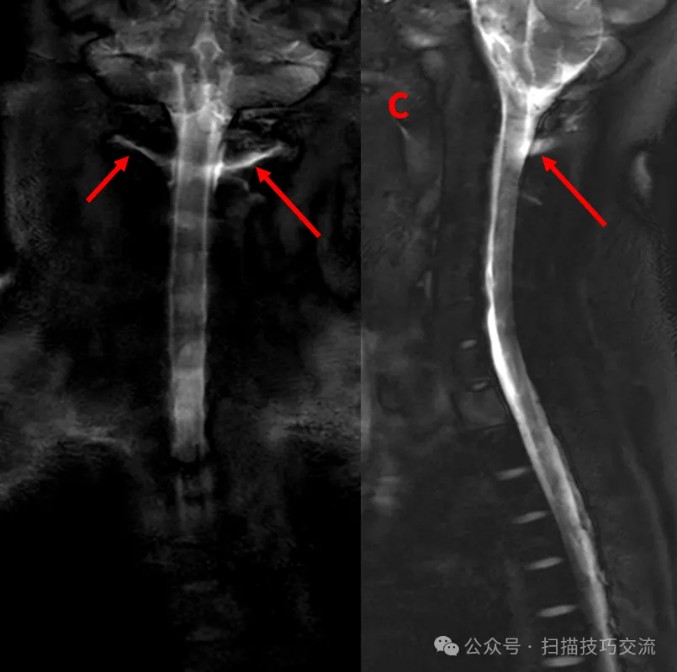

快速的脊髓水成像序列& #40;1s/slice& #41;,试一下,

颈2区域感觉不大对(长箭)。

加个COR 2D MRM对照一下。扫描参数界面:

有点感觉了吧。